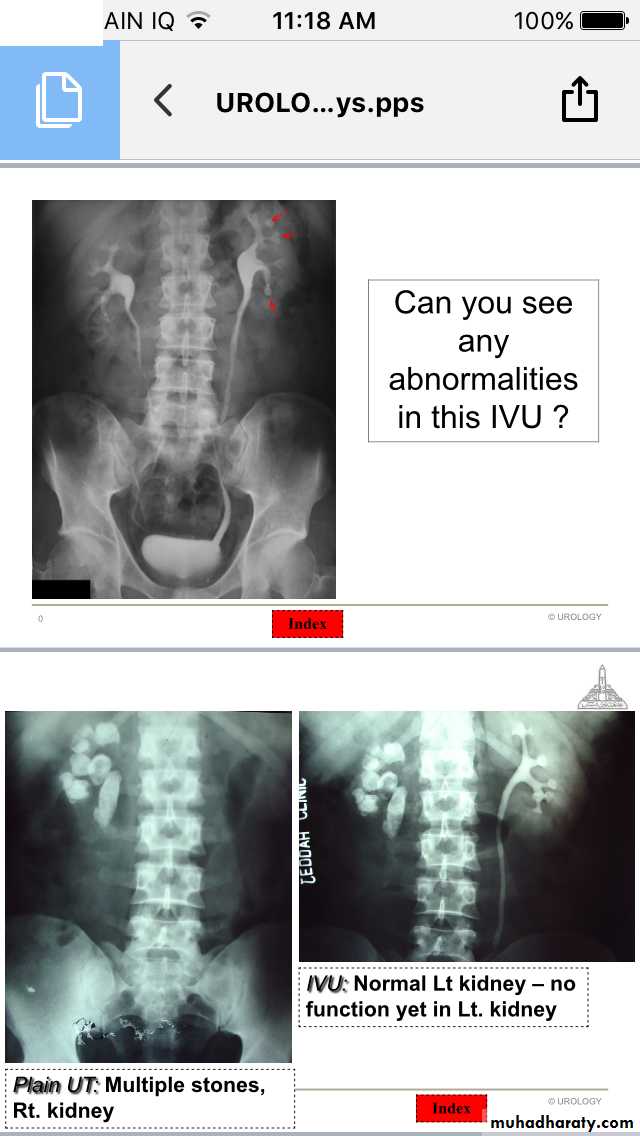

Renal stones

Ureteric stones